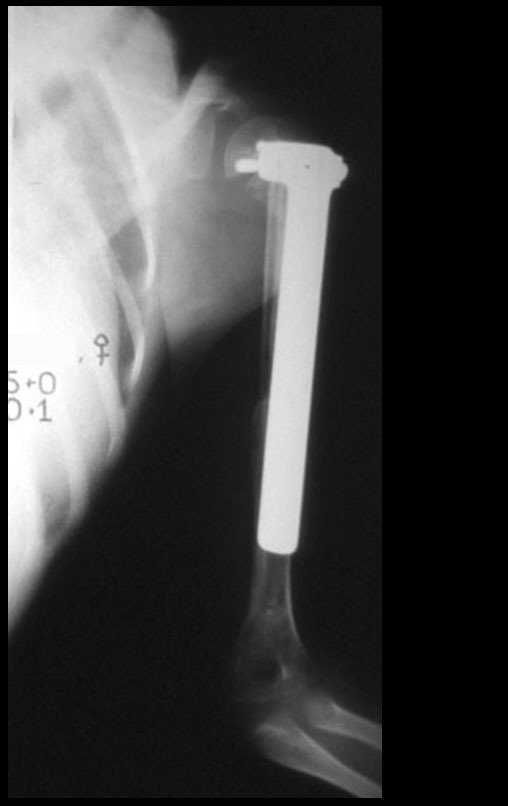

Ewing sarcoma of the humerus in children. A four-year-old and five-month-old patient presented with pain and a tumor in the left humerus in January 1991. The biopsy revealed Ewing’s sarcoma. Staging did not reveal another focus. He underwent treatment with neoadjuvant chemotherapy, showing a good radiographic response to treatment, with mineralization of the lesion and angular deformity due to neoplastic plasticity, figures 1 to 4.

The control radiograph one month postoperatively and the function of the operated limb are shown in figures 11 to 14.